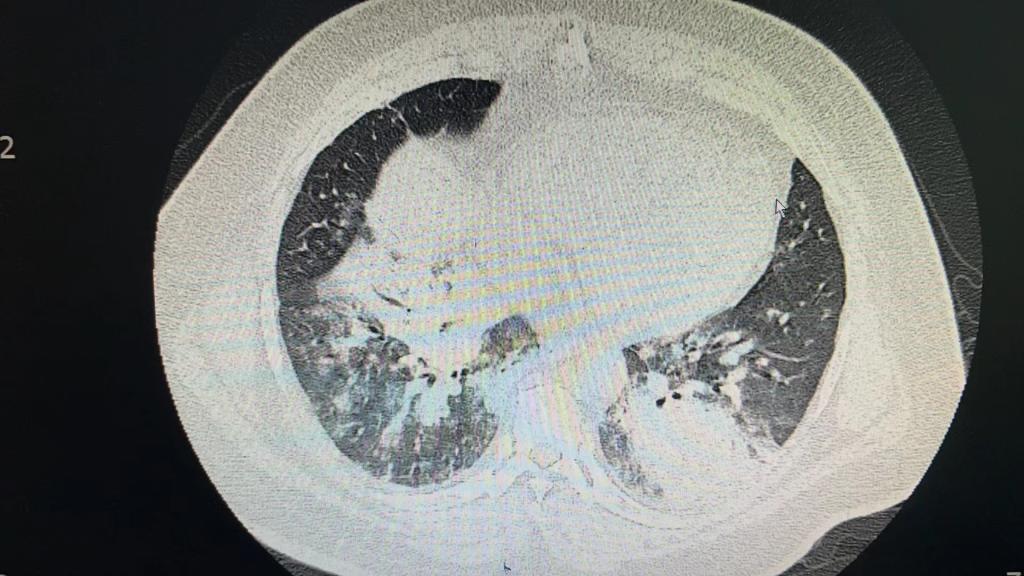

患者以“发热6天伴呼吸衰竭”从外院转入我院EICU,CT呈“白肺”样改变,入院后气管插管呼吸机辅助通气,氧浓度100%,血氧饱和度不到80%,氧合指数只有50,生命岌岌可危。千钧一发之际,ECMO团队迅速全面的病情评估后,紧急启用ECMO支持治疗。

图1 图2腺病毒感染的白肺